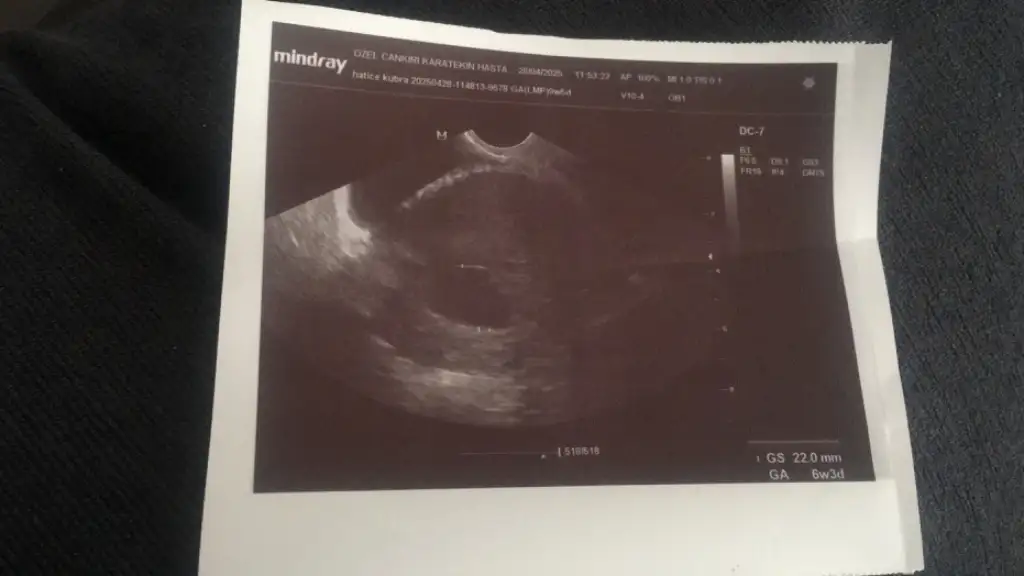

Canım yolksaç var dedilerse bebek de oluşur ben daha önce boş gebelik geçirdim benim şöyle olmuştu kese göründü 5 haftalık 6mm kese çok güzel falan demişti on gün sonra gel dedi gittim baktı böyle morali düştü ben direk sorun mı var dedim bebeği bırak kese hiç büyümemiş dedi en azından kese büyüse bebeğin oluşmasını bekleriz falan dedi Oyüzden direk boş gebelik bu kürtaj dedi ve kürtaj oldum yani bende yolksac yoktuMerhaba! Arkadaşlar dün gıttım doktora devlet hastanesınde doktor 10 gün sonra gel demıstı 7 gün sonra gıttım kesenın ıcınde bır çıkıntı var dedı bebek varmı dıye sorduğumda haftaya gel dedı özele gıttım vajınal bakıldı henüz bebek yok dedı 22 mm kese yazıyor ulstorson kağıdında 6+3 dedı haftaya gel dedı cok korkuyorum bos gebelık olabılır dedı erkenmı devlette bır çıkıntı var dedı kafam karıstı 1 bucuk hafta önce gıttıgımde yolksac mevcut yazmıştı raporda tecrübesi olanlar yardım edebılırmı hafıf kanama alanın var dedı ılac verdı ama benım normal kanamam lekelenmem hıc olmadı aşırı baş agrısı ıcın gıtmıstım yardımcı olacak varmı endıselıyım

Ultroson kağıdında sağ üstte hafıf bır çıkıntı gözüküyormu sizce bızmı yanlıs yorumluyoruzCanım yolksaç var dedilerse bebek de oluşur ben daha önce boş gebelik geçirdim benim şöyle olmuştu kese göründü 5 haftalık 6mm kese çok güzel falan demişti on gün sonra gel dedi gittim baktı böyle morali düştü ben direk sorun mı var dedim bebeği bırak kese hiç büyümemiş dedi en azından kese büyüse bebeğin oluşmasını bekleriz falan dedi Oyüzden direk boş gebelik bu kürtaj dedi ve kürtaj oldum yani bende yolksac yoktu

Ben pek göremedim ama yüzük şeklinde bir şekil varsa yolksac oluyorUltroson kağıdında sağ üstte hafıf bır çıkıntı gözüküyormu sizce bızmı yanlıs yorumluyoruz

6+3 de belli oluyormu boş gebelik olup olmadigi ben ayın 12 snde gittim kese gorunuyor 23 nde gel kalp atışı na bakalım dedi yani boş gebelik olsa o zaman belli olur muydu o zaman doktor bana 6 haftalık dediMerhaba! Arkadaşlar dün gıttım doktora devlet hastanesınde doktor 10 gün sonra gel demıstı 7 gün sonra gıttım kesenın ıcınde bır çıkıntı var dedı bebek varmı dıye sorduğumda haftaya gel dedı özele gıttım vajınal bakıldı henüz bebek yok dedı 22 mm kese yazıyor ulstorson kağıdında 6+3 dedı haftaya gel dedı cok korkuyorum bos gebelık olabılır dedı erkenmı devlette bır çıkıntı var dedı kafam karıstı 1 bucuk hafta önce gıttıgımde yolksac mevcut yazmıştı raporda tecrübesi olanlar yardım edebılırmı hafıf kanama alanın var dedı ılac verdı ama benım normal kanamam lekelenmem hıc olmadı aşırı baş agrısı ıcın gıtmıstım yardımcı olacak varmı endıselıyım